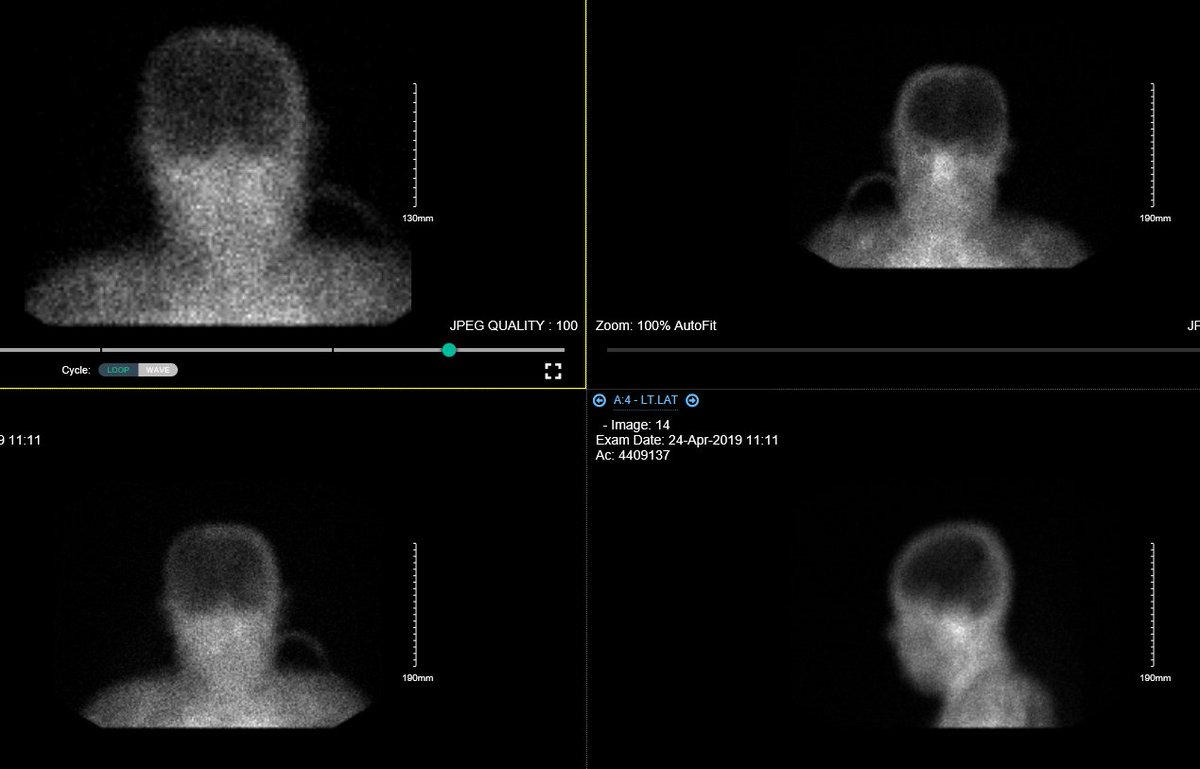

47 male in ICU. #Brain_imaging is done. Diagnosis ? #MedTwitter #neuroscience